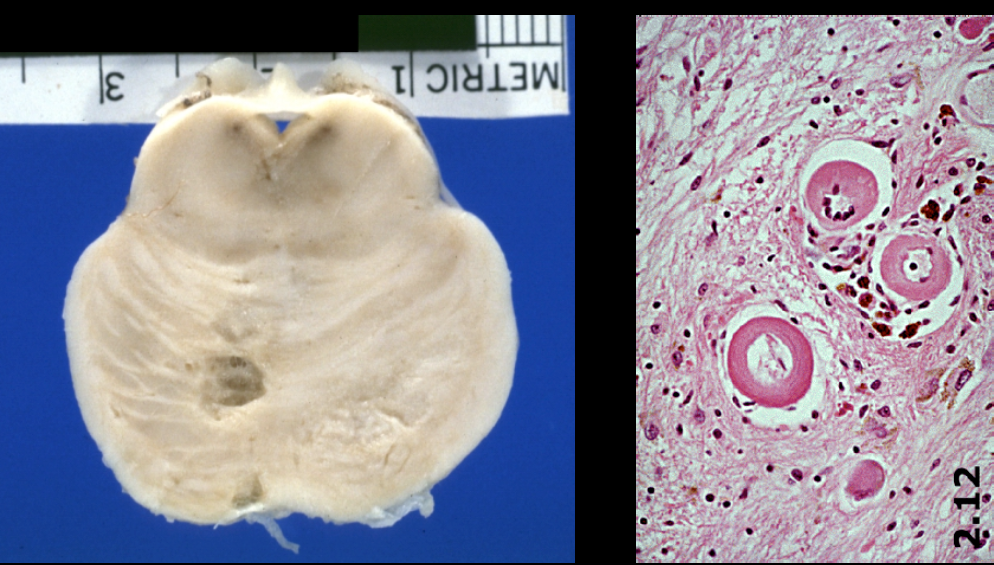

What type of stroke caused this? What is the underlying vascular problem identified on pathology?

Lacunar infarction

• Infarctions ranging in size from 1 mm to 1.5 cm (arrow)

• Classically, the walls of small arteries become thickened from the formation of hyalinemembranes (lipohyalinosis) (circle)

– Caused by chronic hypertension